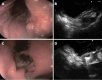

Methods: Forty-one patients with gastric cancer (12 early stage and 29 advanced stage) proved by esophagogastroduodenoscopy and biopsies preoperatively evaluated with EUS according to TNM (1997) classification of International Union Contrele Cancer (UICC). Pentax EG-3630U/Hitachi EUB-525 echo endoscope with real-time ultrasound imaging linear scanning transducers (7.5 and 5.0 MHz) and Doppler information was used in the current study. EUS staging procedures for tumor depth of invasion (T stage) were performed according to the widely accepted five-layer structure of the gastric wall. All patients underwent surgery. Diagnostic accuracy of EUS for TNM staging of gastric cancer was determined by comparing preoperative EUS with subsequent postoperative histopathologic findings.

Results: The overall diagnostic accuracy of EUS in preoperative determination of cancer depth of invasion was 68.3% (41/28) and 83.3% (12/10), 60% (20/12), 100% (5/5), 25% (4/1) for T1, T2, T3, and T4, respectively. The rates for overstaging and understaging were 24.4% (41/10), and 7.3% (41/3), respectively. EUS tended to overstage T criteria, and main reasons for overstaging were thickening of the gastric wall due to perifocal inflammatory change, and absence of serosal layer in certain areas of the stomach. The diagnostic accuracy of metastatic lymph node involvement or N staging of EUS was 100% (17/17) for N0 and 41.7% (24/10) for N+, respectively, and 66% (41/27) overall. Misdiagnosing of the metastatic lymph nodes was related to the difficulty of distinguishing inflammatory lymph nodes from malignant lymph nodes, which imitate similar echo features. Predominant location and distribution of tumors in the stomach were in the antrum (20 patients), and the lesser curvature (17 patients), respectively. Three cases were found as surgically unresectable (T4 N+), and included as being correctly diagnosed by EUS.